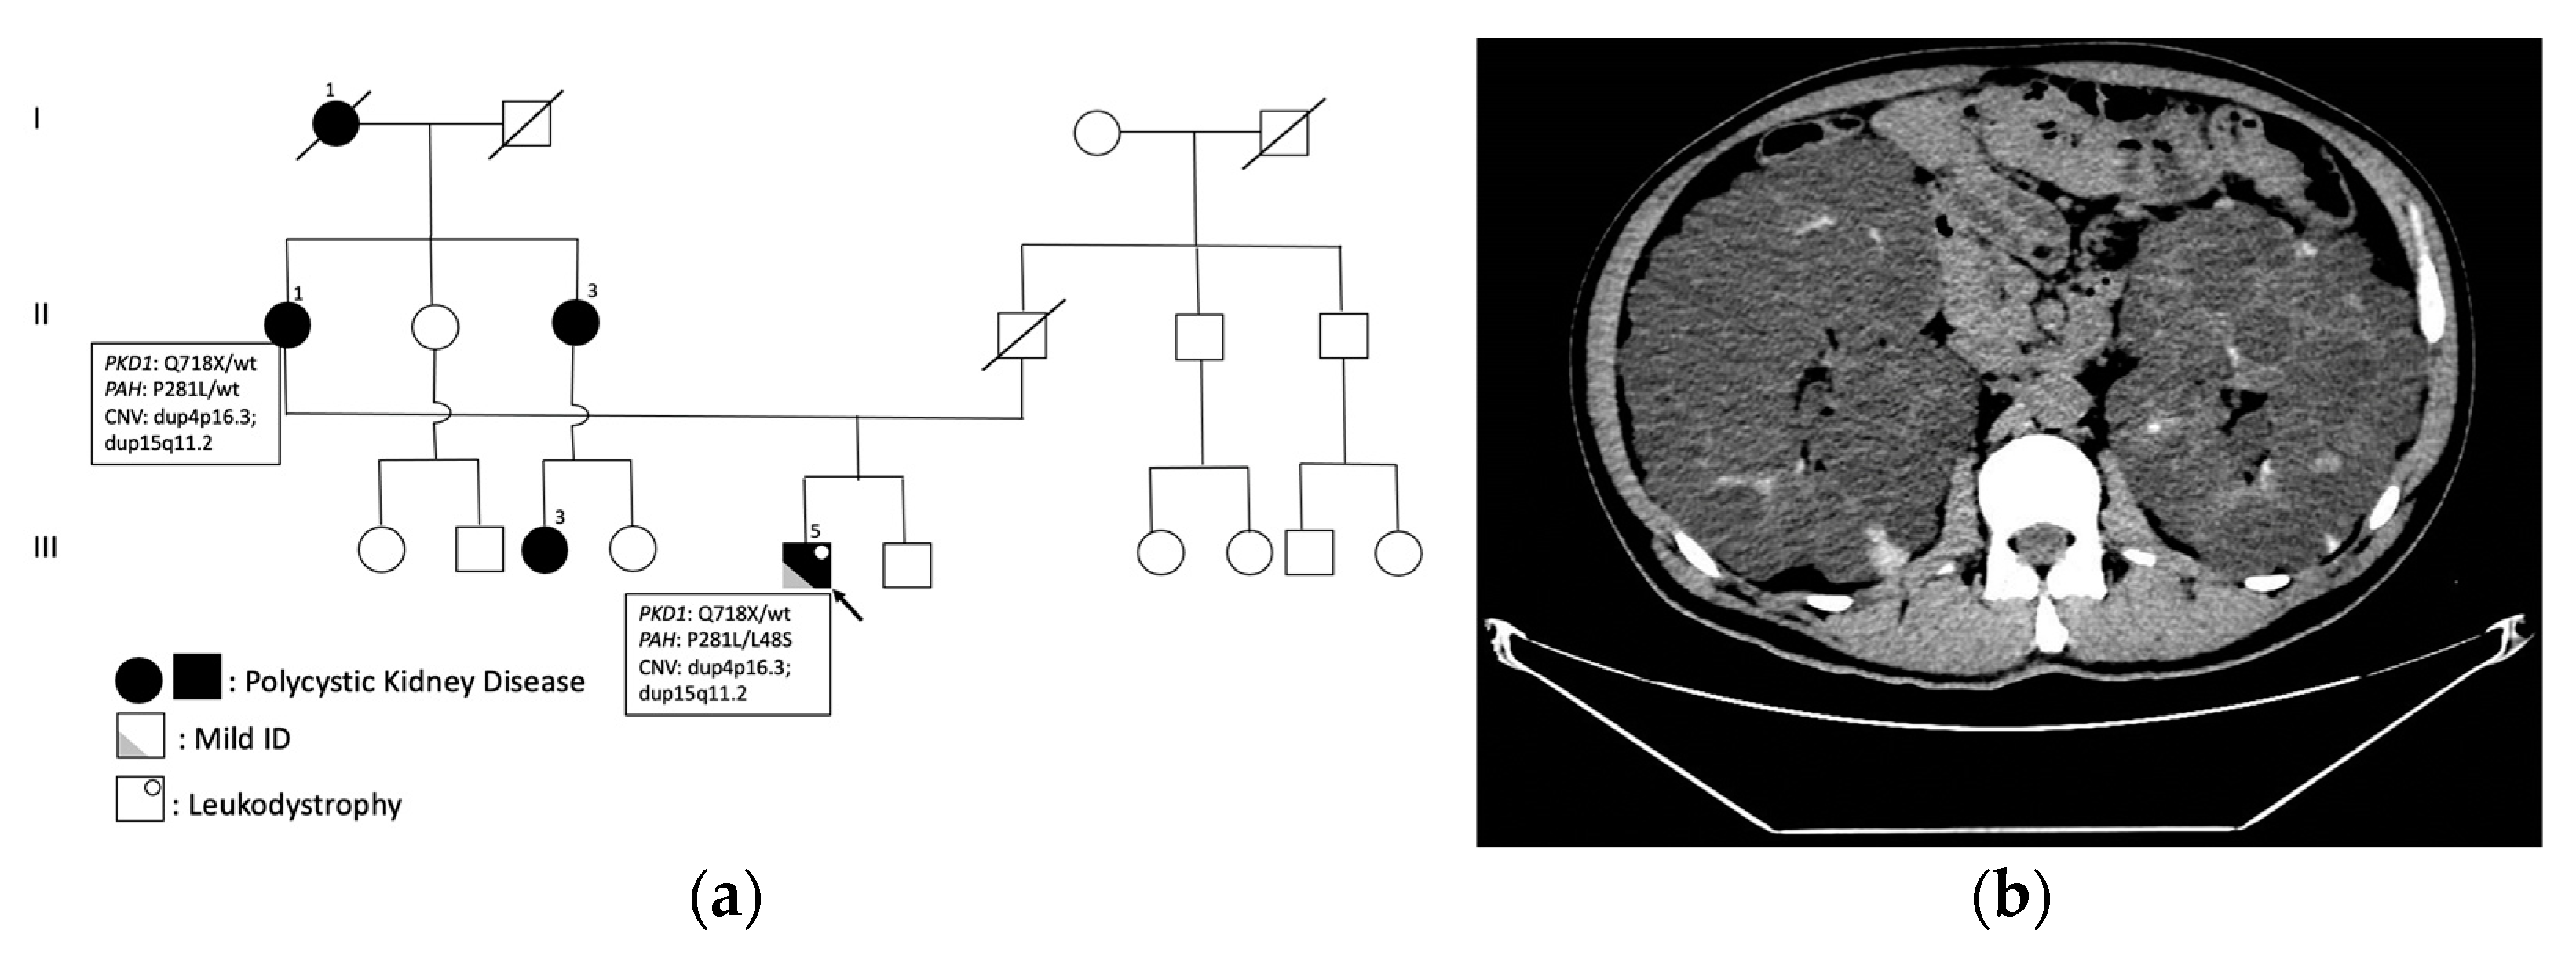

Pasquetti, D.; Gazzellone, A.; Rossi, S.; Orteschi, D.; L’Erario, F.F.; Concolino, P.; Minucci, A.; Dionisi-Vici, C.; Genuardi, M.; Silvestri, G.; et al. Triple Genetic Diagnosis in a Patient with Late-Onset Leukodystrophy and Mild Intellectual Disability. Int. J. Mol. Sci. 2024, 25, 495. https://doi.org/10.3390/ijms25010495